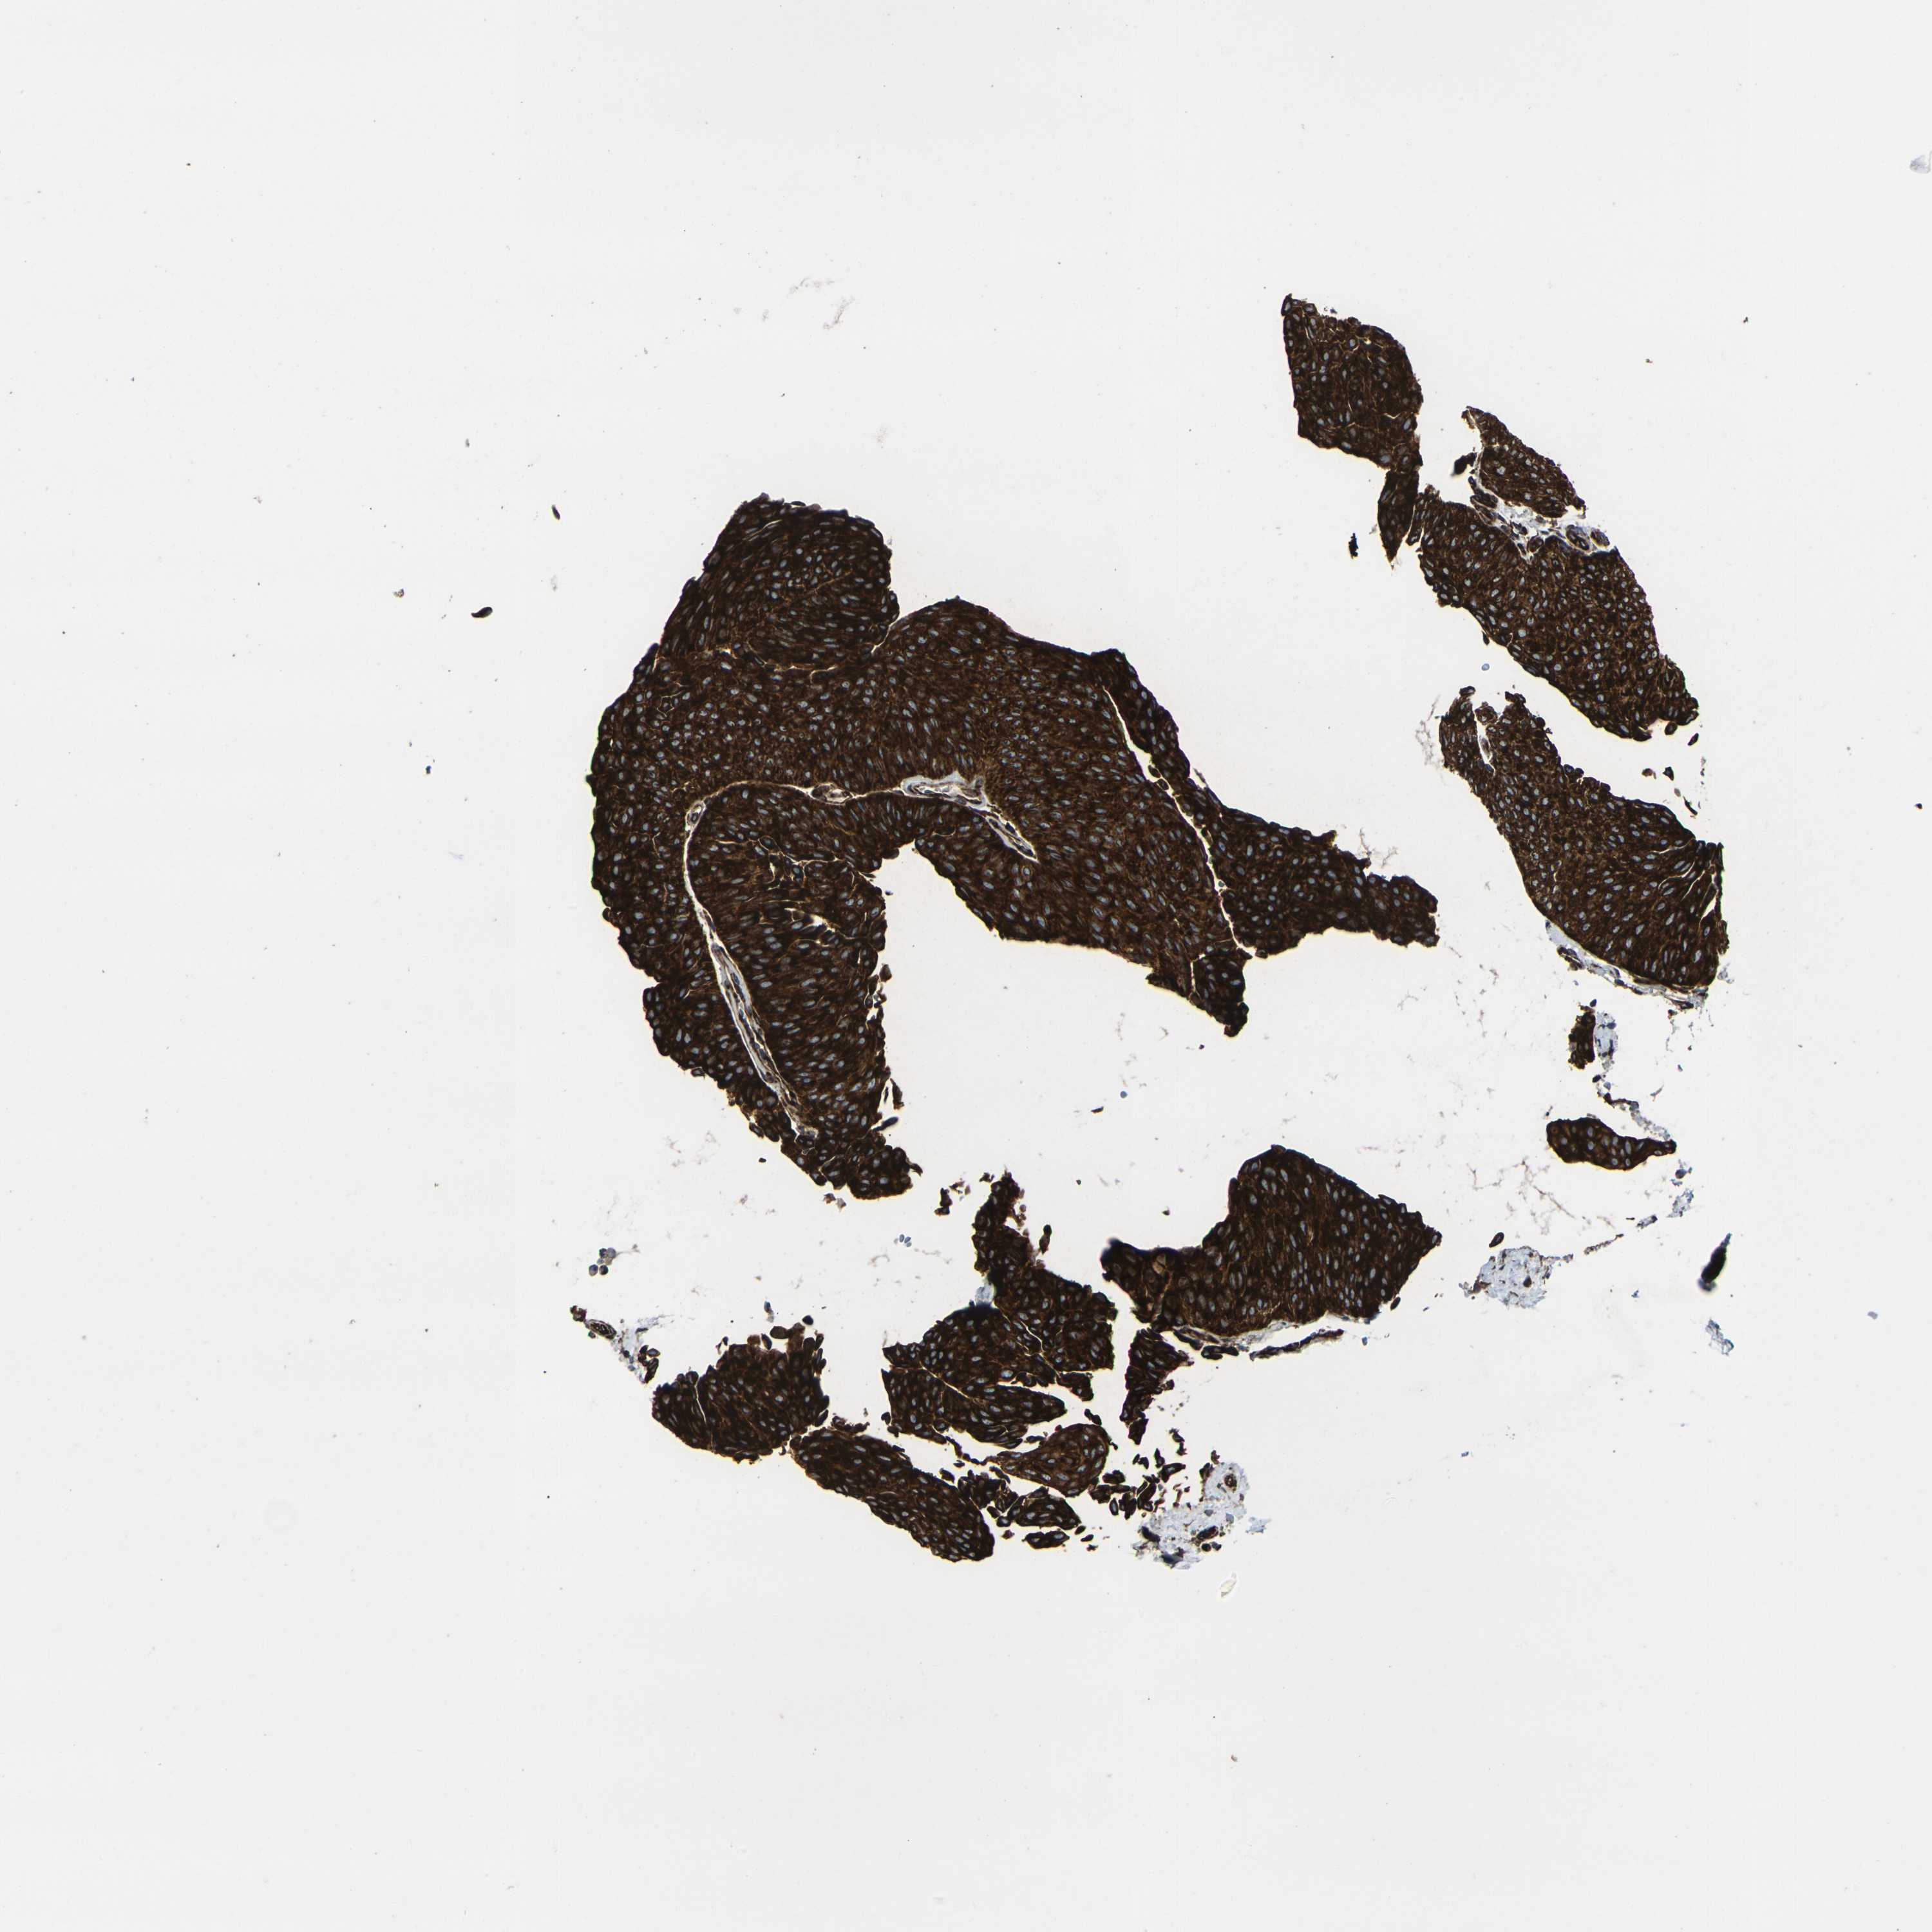

UROTHELIAL CANCER - Protein expressioni

A mouse-over function shows sample information and annotation data. Click on an image to view it in a full screen mode. Samples can be filtered based on level of antibody staining by selecting one or several of the following categories: high, medium, low and not detected. The assay and annotation is described here.

Antibody stainingi

Antibody staining in the annotated cell types in the current human tissue is reported as not detected, low, medium, or high, based on conventional immunohistochemistry profiling in selected tissues. This score is based on the combination of the staining intensity and fraction of stained cells.

Each image is clickable and will lead to virtual microscopy that enables deeper exploration of all samples and also displays staining intensity scores, fraction scores and subcellular localization as well as patient and tissue information for each sample.

Antibody HPA014063

Staining

High

Medium

Low

Not detected

Intensity

Strong

Moderate

Weak

Negative

Quantity

>75%

75%-25%

<25%

None

Location

Nuclear

Cytoplasmic/membranous

Cytoplasmic/membranous,nuclear

Urothelial carcinoma, Low grade

Urothelial carcinoma, High grade